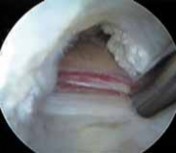

TECH FIG 2•

Arthroscopic view from the peripheral compartment of a right hip.

A.

A window (

arrows

) has been created through the thin medial capsule, exposing the iliopsoas tendon (

) anterior to the femoral head (

FH

).

B.

The tendinous portion is released with a basket.

C.

The final fibers are débrided with a power shaver.

D.

Through the capsular window (

) the tendon has been completely released, preserving the muscular fibers (

). The relation between the capsular window and the acetabular labrum (

AL

) and femoral

D

head (

) is identified. (Courtesy of J. W. Thomas Byrd, MD.)